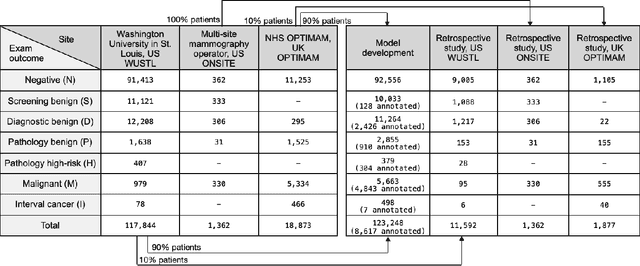

A deep learning algorithm for reducing false positives in screening mammography

Apr 13, 2022

Screening mammography improves breast cancer outcomes by enabling early detection and treatment. However, false positive callbacks for additional imaging from screening exams cause unnecessary procedures, patient anxiety, and financial burden. This work demonstrates an AI algorithm that reduces false positives by identifying mammograms not suspicious for breast cancer. We trained the algorithm to determine the absence of cancer using 123,248 2D digital mammograms (6,161 cancers) and performed a retrospective study on 14,831 screening exams (1,026 cancers) from 15 US and 3 UK sites. Retrospective evaluation of the algorithm on the largest of the US sites (11,592 mammograms, 101 cancers) a) left the cancer detection rate unaffected (p=0.02, non-inferiority margin 0.25 cancers per 1000 exams), b) reduced callbacks for diagnostic exams by 31.1% compared to standard clinical readings, c) reduced benign needle biopsies by 7.4%, and d) reduced screening exams requiring radiologist interpretation by 41.6% in the simulated clinical workflow. This work lays the foundation for semi-autonomous breast cancer screening systems that could benefit patients and healthcare systems by reducing false positives, unnecessary procedures, patient anxiety, and expenses.